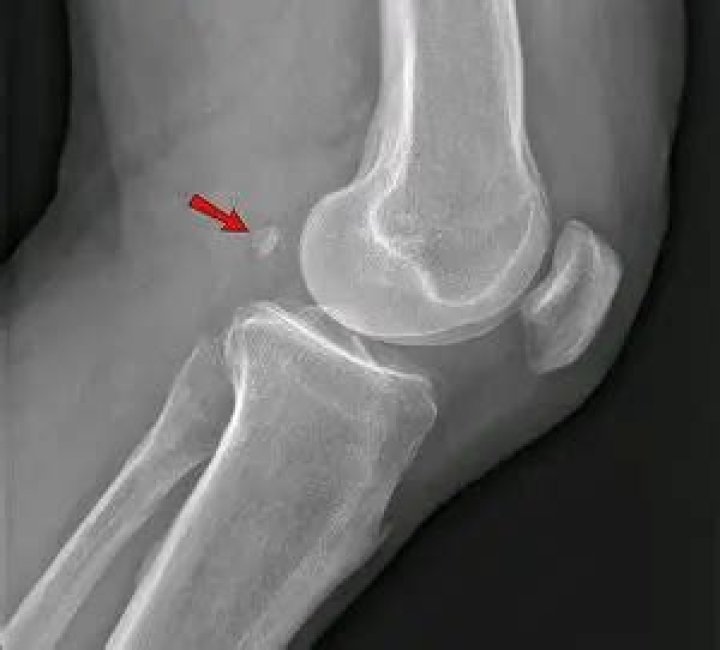

The fabella is a small sesamoid bone found in some mammals embedded in the tendon of the lateral head of the gastrocnemius muscle behind the lateral condyle of the femur. It is an accessory bone, an anatomical variation present in 39% of humans.

The fabella is a sesamoid bone located behind the lateral femoral condyle. It is common in non‐human mammals, but the prevalence rates in humans vary from 3 to 87%.

The fabella is located in the posterior aspect of the knee where lines of tensile stress intersect. It articulates with the posterior part of the articular surface of the lateral femoral condyle and is embedded in the muscular fibres of the gastrocnemius muscle [5].

What is a fabella in medicine?

Medical Definition of fabella

: a small fibrocartilage ossified in many animals and sometimes in humans in the tendon of the gastrocnemius muscle, behind one or both of the femoral condyles.